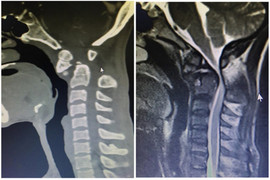

Anh H.V.S. (41 tuổi, trú tại huyện Thanh Sơn, Phú Thọ) nhập viện trong tình trạng đau cột sống cổ, hạn chế vận động, yếu tứ chi không đi lại được, tê bì mất cảm giác từ ngang ngực trở xuống.